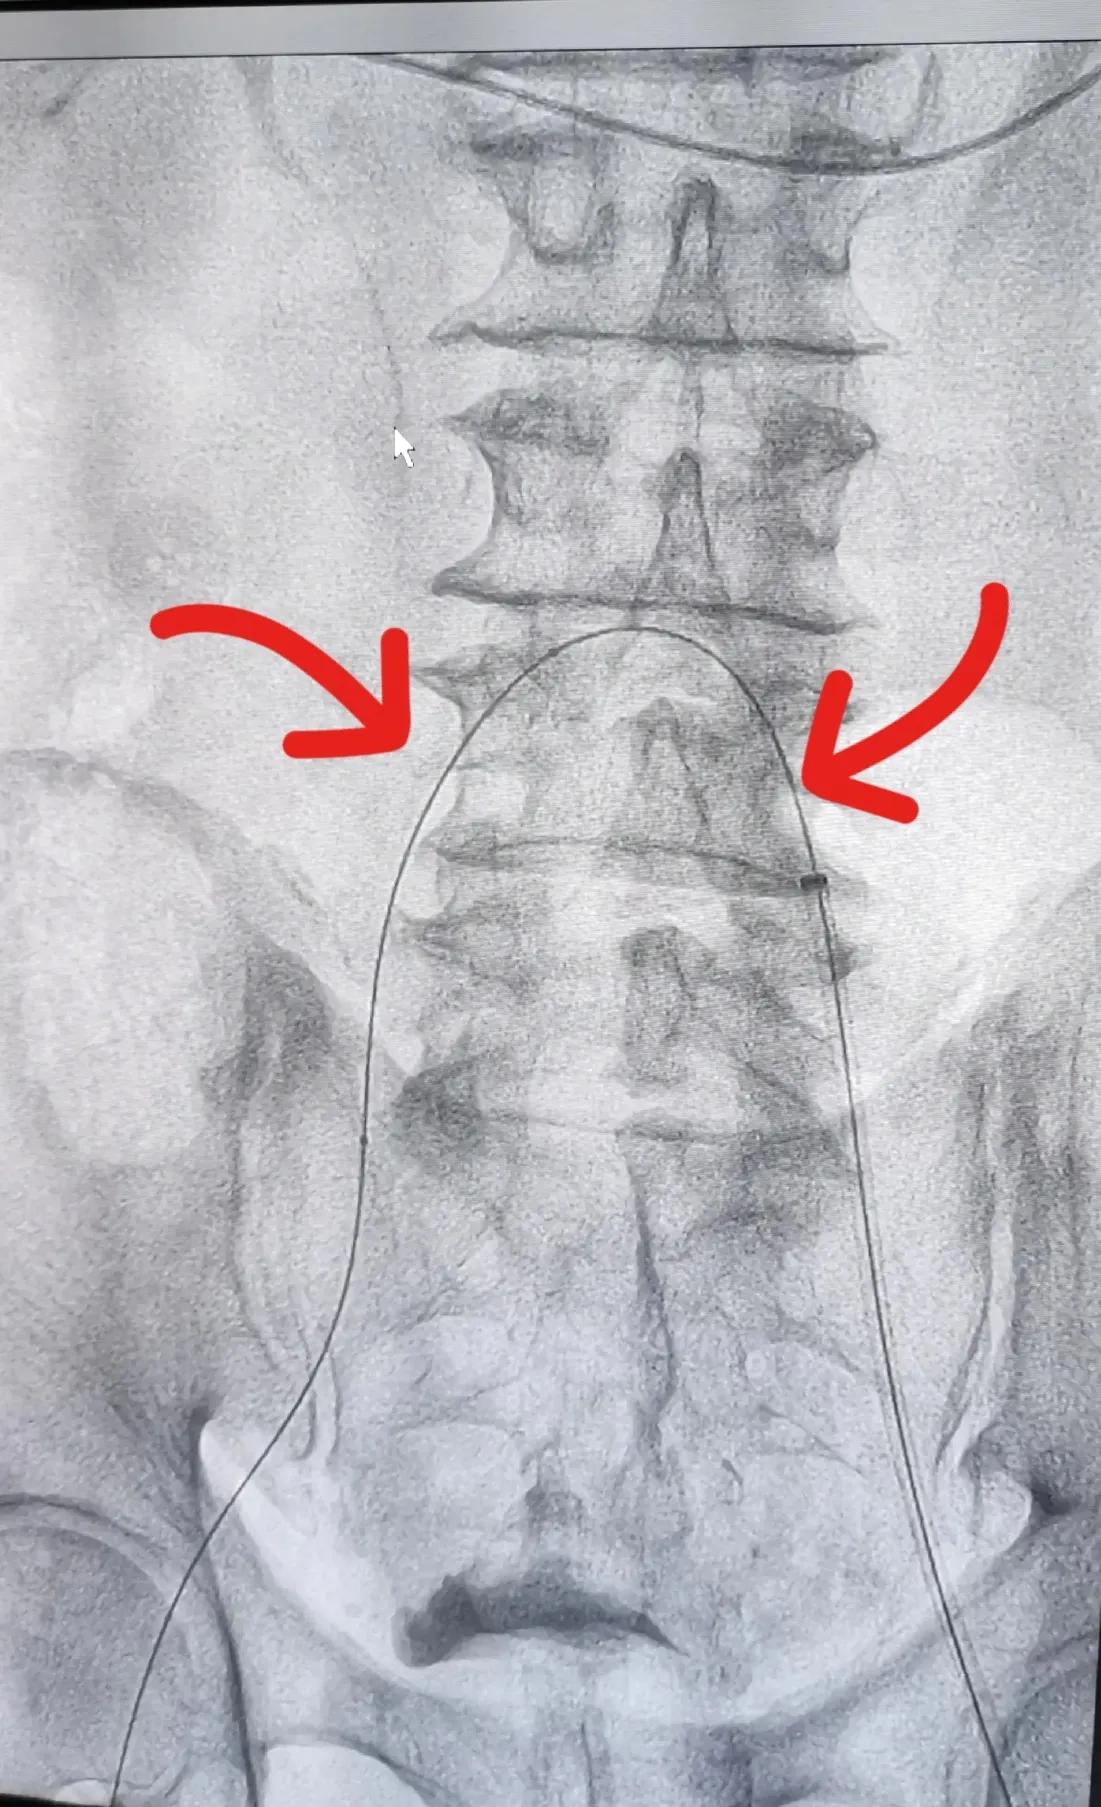

图三:红色箭头所指是右侧髂动脉闭塞后,介入医生将导丝放入两侧股动脉内,作为植入支架的通路

图一至图五是2022年9月初浙江普陀医院(公立)骨科医生对退休教师李某某髂动脉,股动脉闭塞性动脉硬化进行介入治疗前后血管造影对比。显示血管内支架植入后血管形态非常好,患者出院后术后一个月观察,走路时下肢疼痛完全消失,间歇性跛行症状消失,两下肢功能完全恢复。